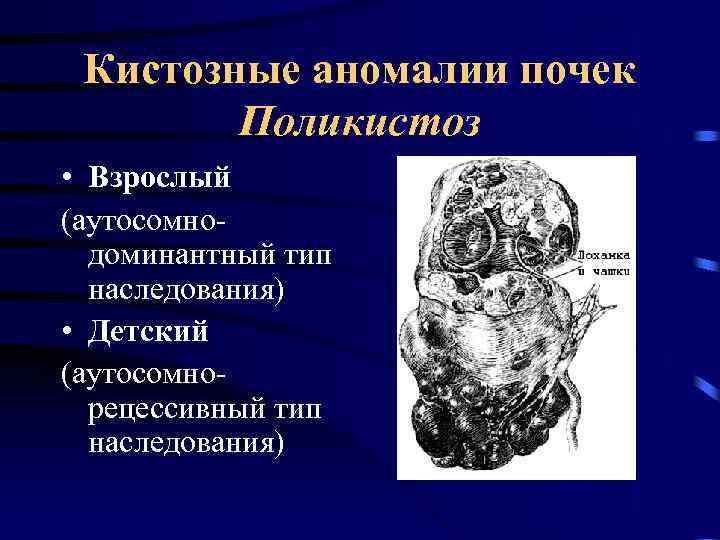

Кистозные аномалии почек Поликистоз • Взрослый (аутосомнодоминантный тип наследования) • Детский (аутосомнорецессивный тип наследования)

Кистозные аномалии почек Поликистоз • Взрослый (аутосомнодоминантный тип наследования) • Детский (аутосомнорецессивный тип наследования)